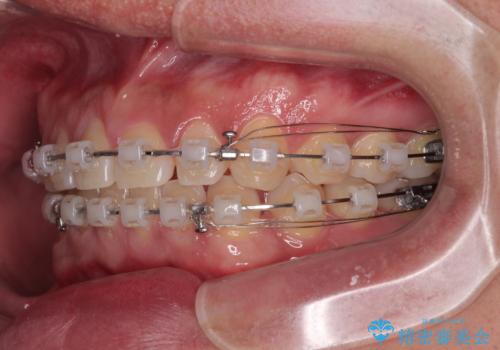

- クリアブラケット

- 1年7ヶ月

飲み込みや話をするときに舌を突出させる癖が強くあり、それが原因でスペースが空いていました。

舌癖を改善するためのトレーニングを行いながら、ワイヤー装置を用いて前歯の隙間を閉じていくこととしました。